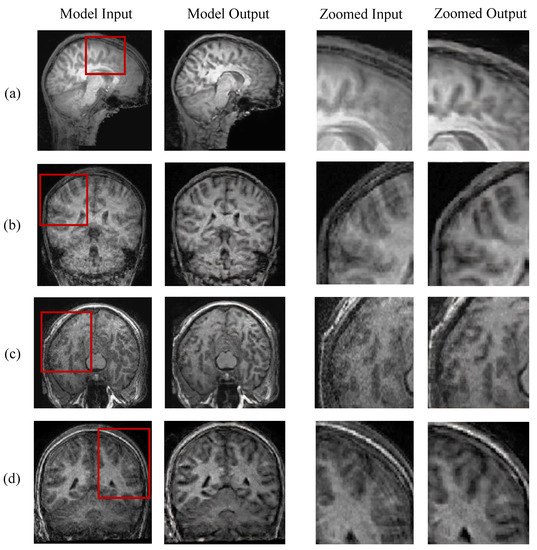

5.3. Evaluation on Real-World Scans